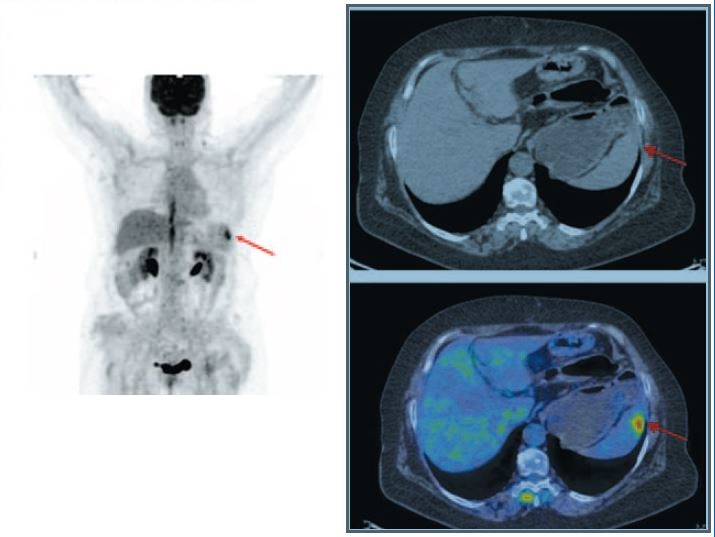

Больная М., 70 лет. В октябре 2019 г. по поводу рака селезеночного угла ободочной кишки стадии IIc pT4bN0M0, осложненного частичной толстокишечной непроходимостью, выполнена левосторонняя гемиколэктомия. При гистологическом исследовании опухоль имела строение изъязвленной умеренно дифференцированной аденокарциномы с прорастанием всех слоев стенки кишки и врастанием в окружающую клетчатку. Лимфоузлы без признаков опухолевого роста. С адъювантной целью проведено 6 циклов ПХТ по схеме FOLFOX. Находилась на диспансерном наблюдении. Клинические признаки болезни отсутствовали. При очередном УЗИ органов брюшной полости в августе 2020 г. в верхнем полюсе селезенки выявлено образование размером 20×13 мм повышенной эхогенности с неровными контурами. Для уточнения диагноза и распространенности опухолевого процесса выполнена ПЭТ/КТ с 18-фтордезокси-глюкозой. По данным ПЭТ/КТ в верхнелатеральном секторе селезенки определяется очаг размером 20×15 мм с повышенной метаболической активностью, SUVmax 5.6. Других очагов накопления РФП не обнаружено. Заключение: солитарный изолированный метастаз в селезенку (рис. 2).

Fig. 2. Patient M., 70 years old. Axial MIP PET and combined PET/CT images showed a focus of increased uptake of radiopharmaceutical in the upper-lateral sector of the spleen, the size was 18×14 mm, SUVmax of 5.6.